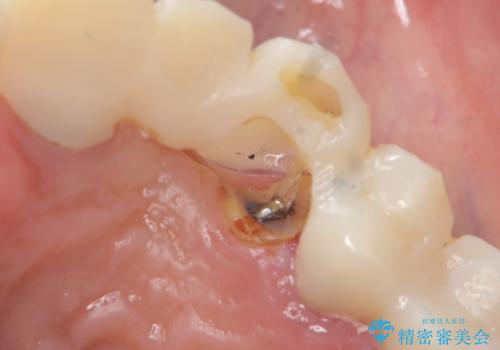

- ブリッジの支台歯であった左上の犬歯が折れたことを主訴に来院された患者様です。

犬歯は歯ぐきの奥深くまで割れており保存不可能な状態でしたが、どうしても抜きたくないとのことでした。

歯を牽引し健全歯質を歯肉縁上まで引き上げ、歯の保存を試みることにしました。